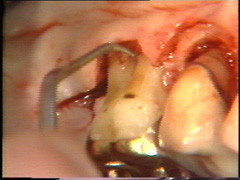

Observese como se

ha eliminado el tejido de granulación en el segundo premolar. |

Eliminación del

tejido de granulación |

Las superficies de la raíz se limpian

(raspado y alisado radicular) cuidadosamente y el tejido de granulación en los

defectos óseos (cráter) es eliminado. En la superficie bucal del segundo premolar hay

un cráter óseo y cálculo en la supericies dental adyacente.

El cálculo del segundo premolar

está unido firmemente a la superficie dental y es un proceso tedioso el

quitarlo.